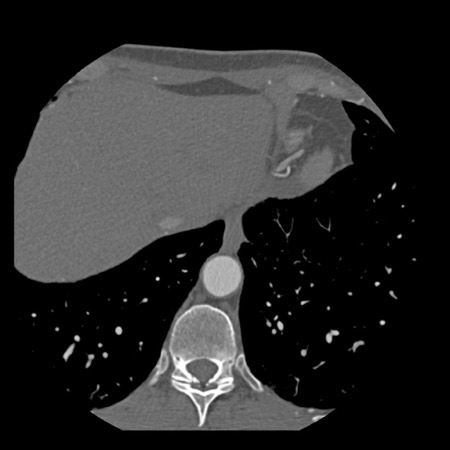

case 4 – CAD-RADS 3/P1/I+ thrombus left ventricle

First, scroll through the CTA images.

How would you describe the findings on the coronary CTA?

The findings are:

- Moderate (50-69%)

stenosis in the proximal LAD caused by a non-calcified plaque. - Variant of

sinoatrial (SA) nodal artery. The artery usually arises from the RCA as a second

branch after the conus artery, however in this case it arises from the LCX,

courses behind the aorta, anastomosing with the right atrium and with a small

branch supplies the SA-node of the heart. - Thrombus in the

apex of the left ventricle. - CTP was performed

in this patient. CTP showed a perfusion defect at stress imaging in the

territory of the LAD (I+), at rest no perfusion defect was visible.

This patient classifies as CAD-RADS 3/P1/I+, which means

this patient requires further investigation.